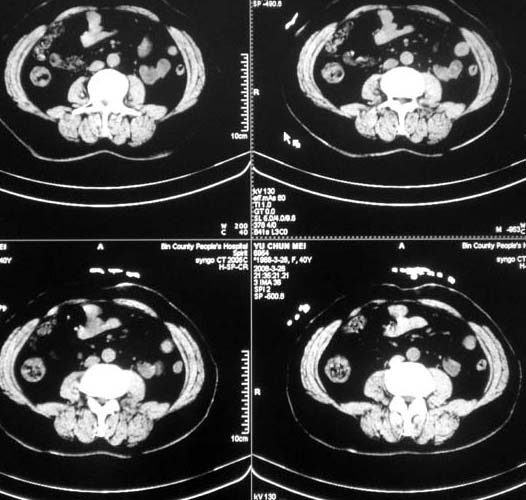

肝内占位性病变:肝血管瘤可能性大,建议必须增强扫描。

肝内多发占位,建议增强检查

肝内多发低密度影,边缘清楚,结合病史考虑:肝血管瘤可能性大,建议必须时增强扫描。